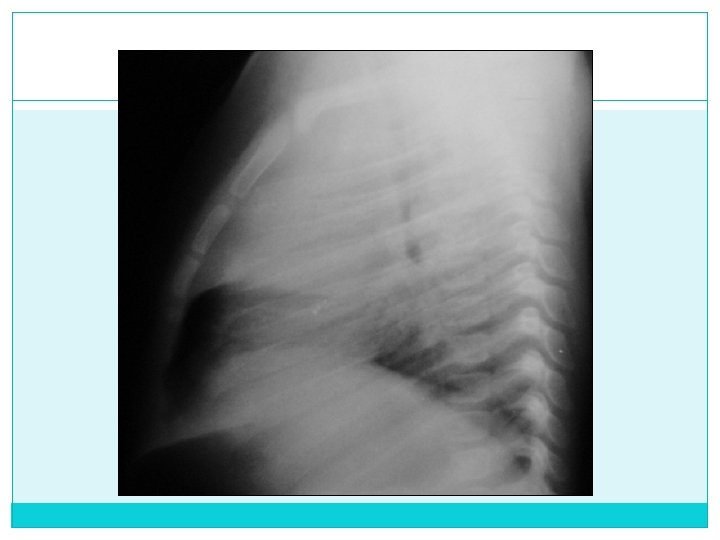

d) Definición Buena: No movimiento del paciente e) Centrado: Frontal: Extremos mediales clavícula equidistantes a línea media (apófisis espinosas) Lateral: Arco Costal posterior de un hemitórax se distancia de su contralateral max. 1 cm